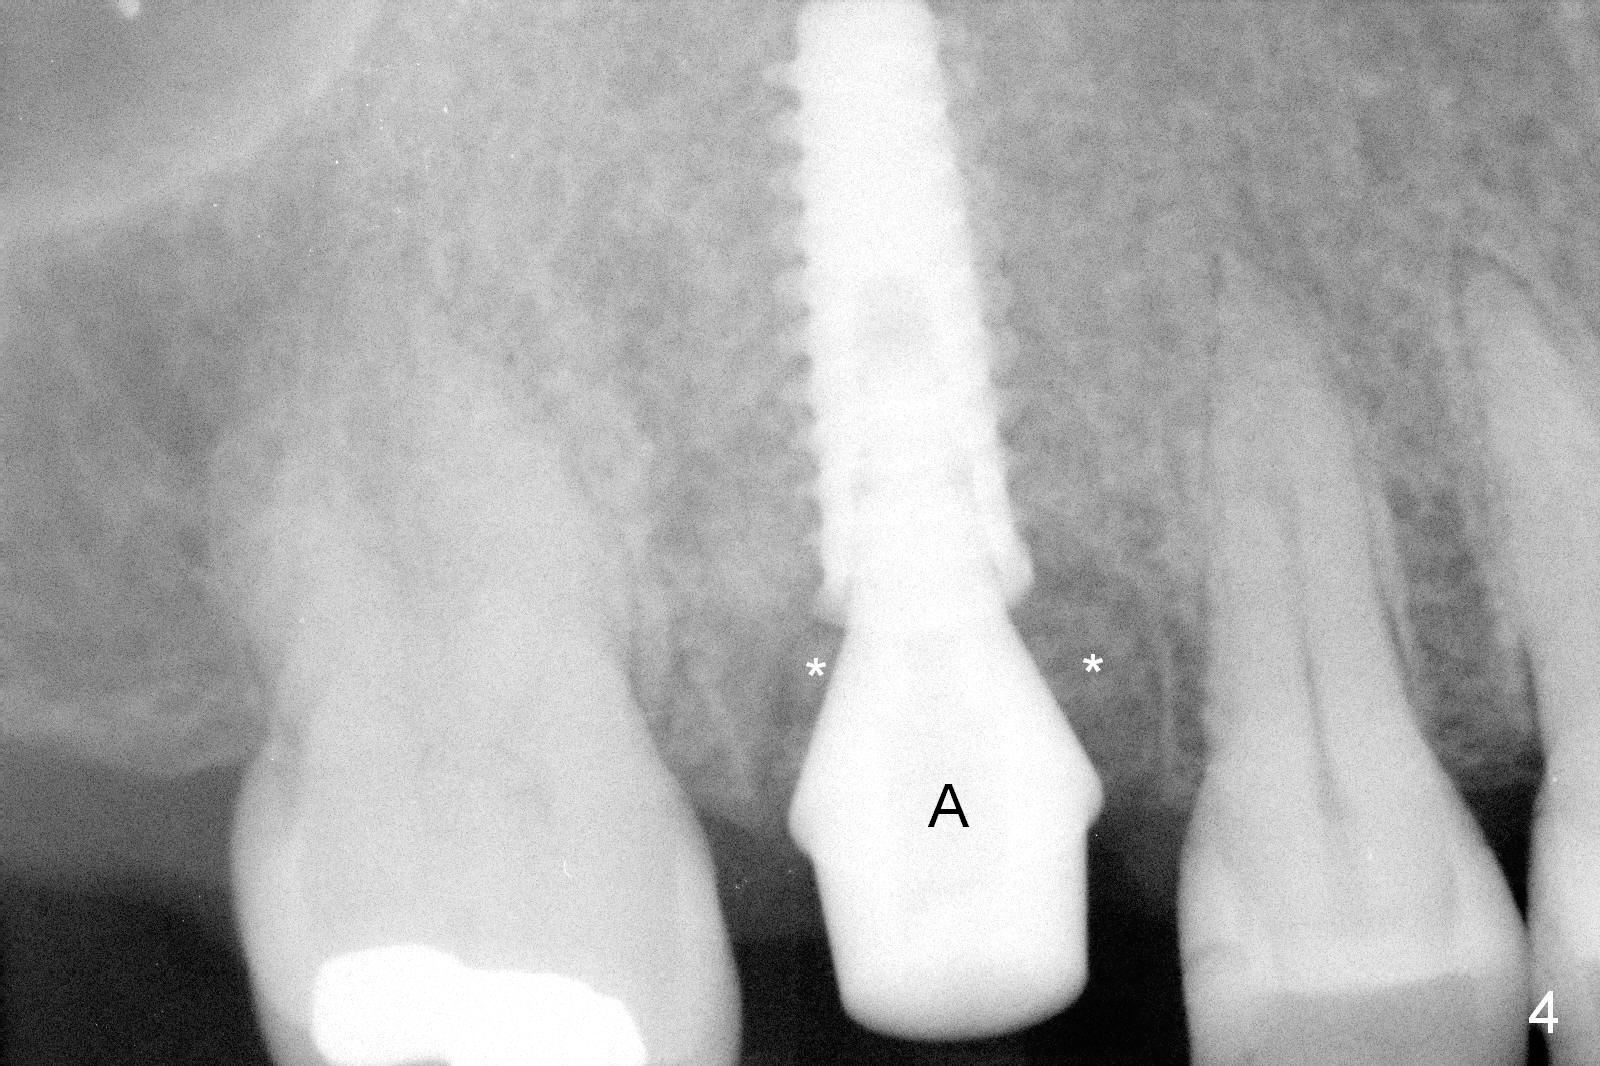

The polyp in the pulpal chamber of the tooth #3 (Fig.1) originates from the distal gingiva. After extraction, buccal plate perforation is found apical to the distobuccal socket. The septum is large (Fig.2 S). Osteotomy is initiated in the middle of the septum with 1.6 mm drill until 3.8 mm Magic Drill (MD) (Fig.3). The last drill is 4.3 mm, followed by 4.8 mm Magic Expander since the palatal wall of the osteotomy is thin after the last drill. A 5x13 mm IBS implant is placed with ~ 45 Ncm. The apical portion of the 3 sockets is filled with Osteogen plug and the coronal portion with autogenous bone (harvested from MD), mixed with allograft and Osteogen (Fig.4 * as well as collagen plug in the most superficial portion of the sockets). A 6.5x4(4) mm pair abutment (Fig.4 A) is placed to hold an immediate provisional in place.